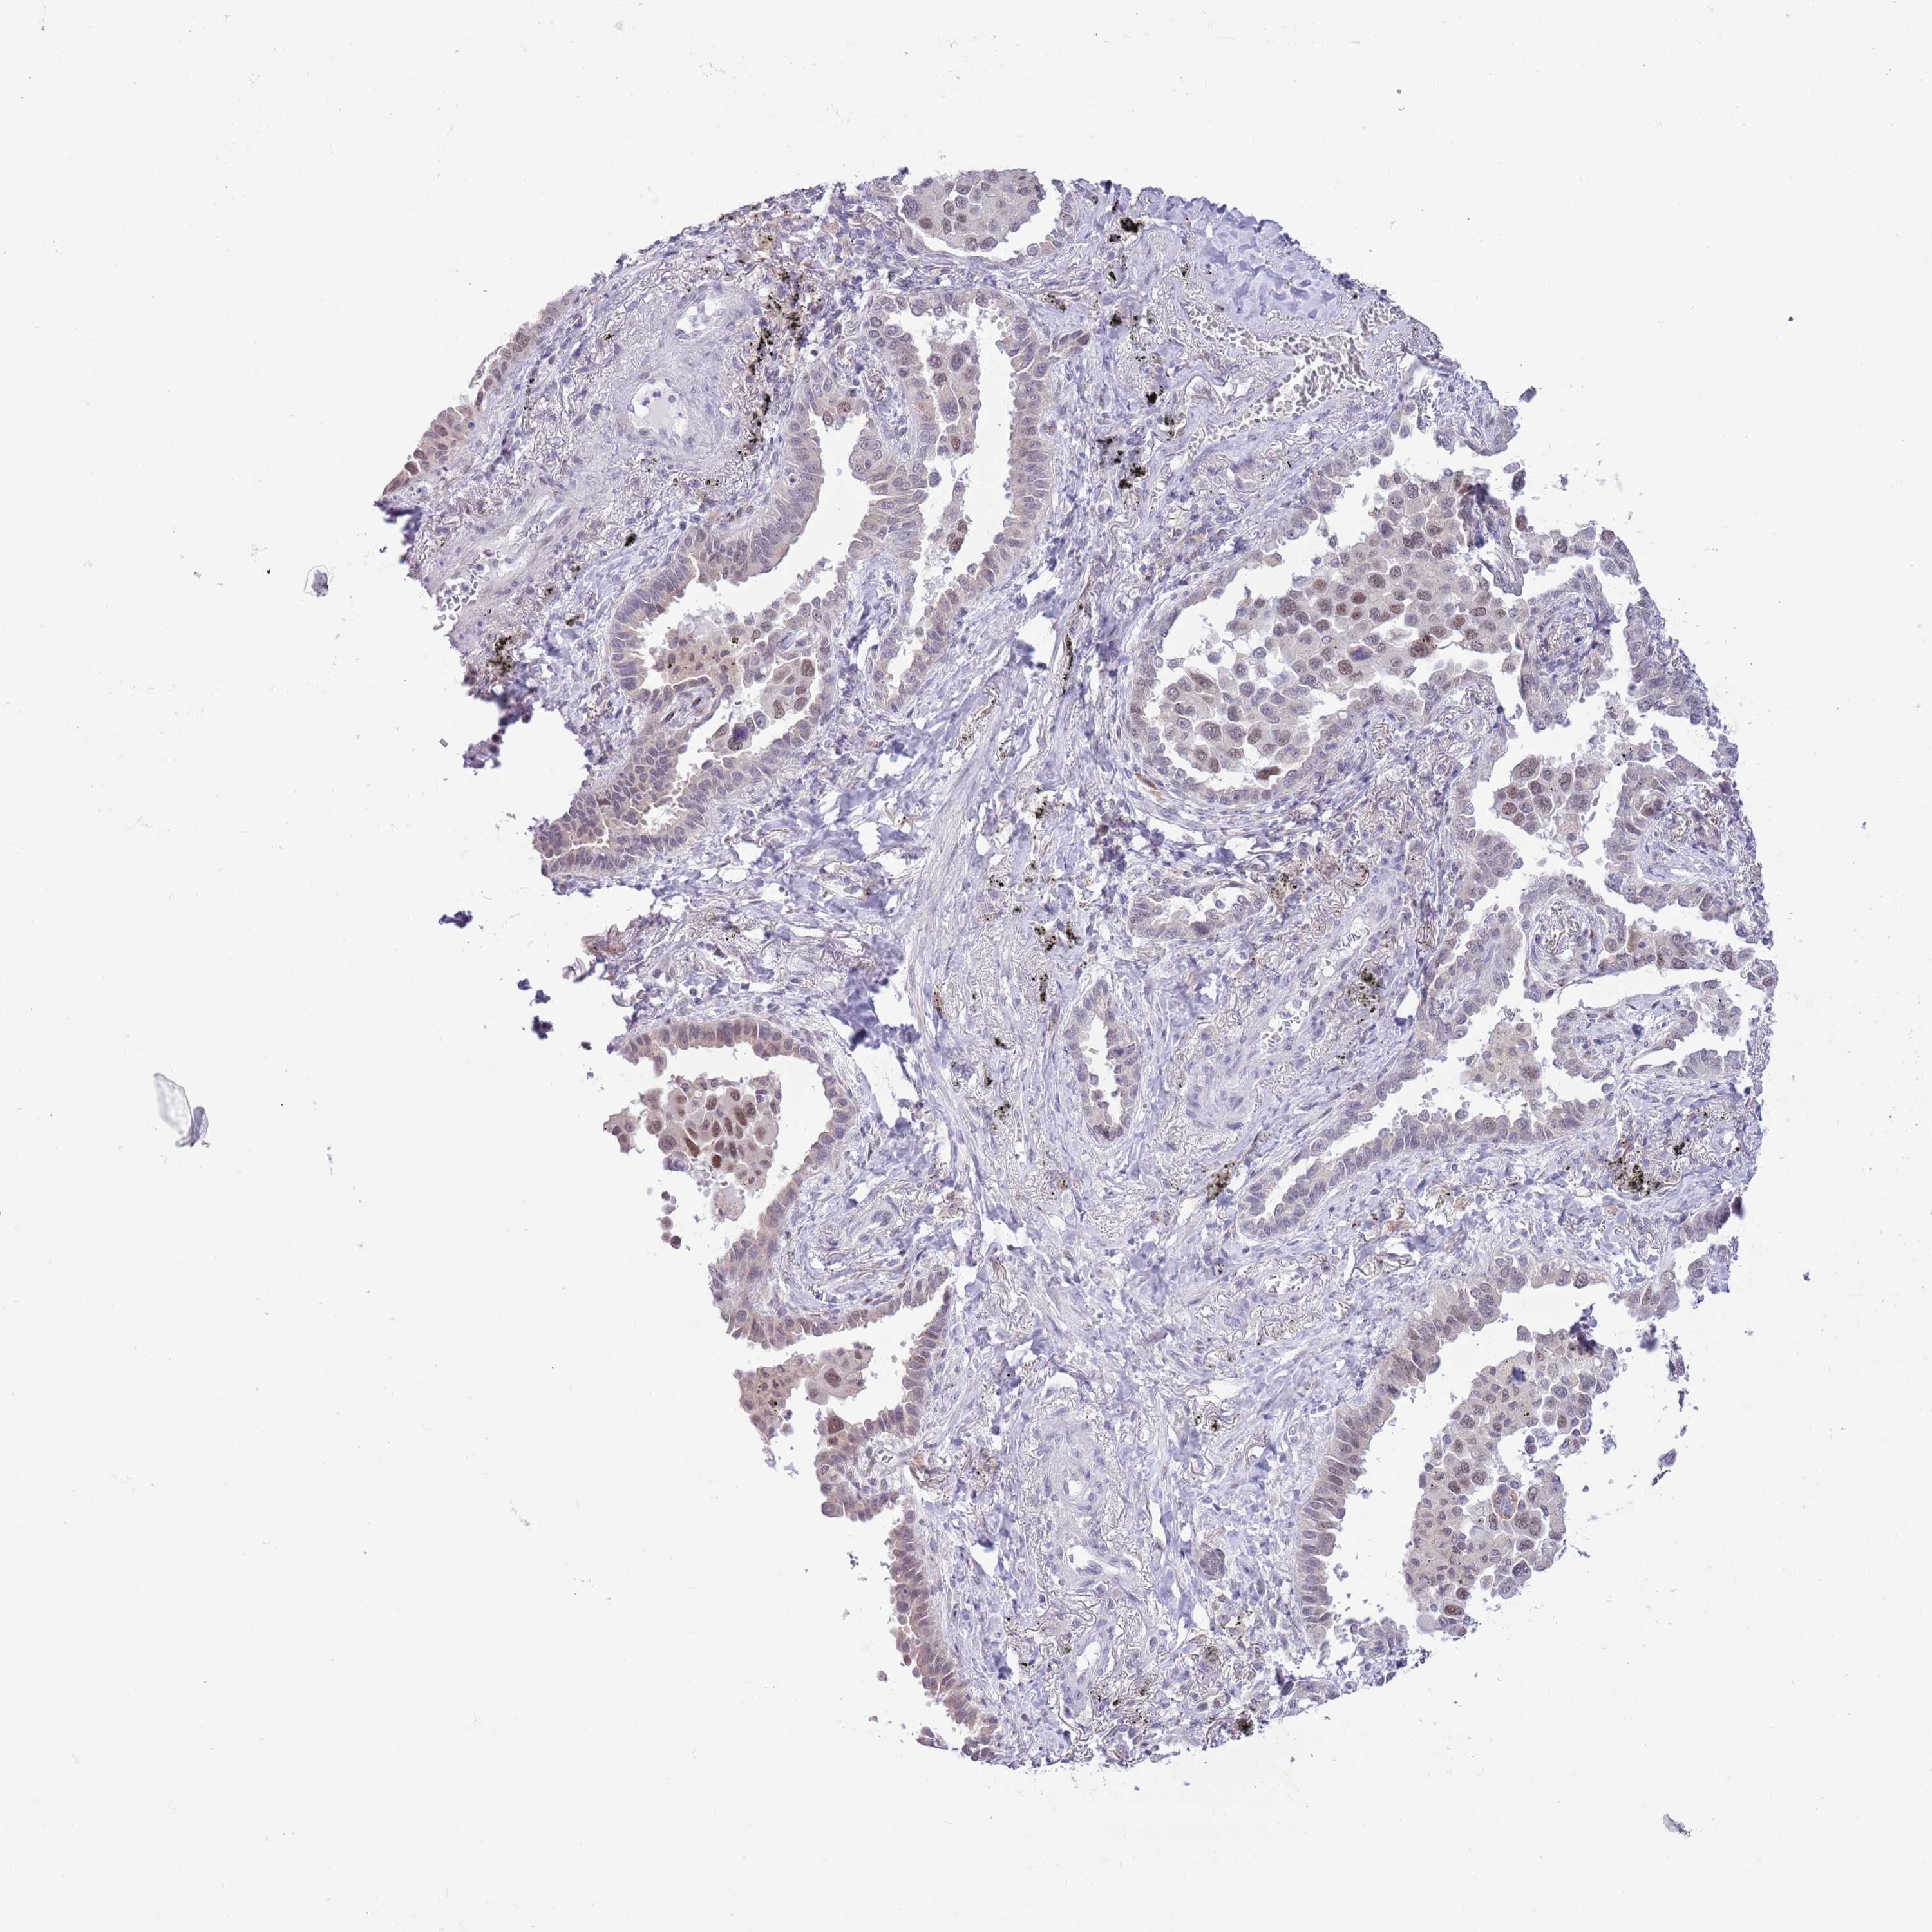

CANCER LUNG CANCER Show tissue menu

LUAD TCGA LUAD VALIDATION LUSC TCGA LUSC VALIDATION PROTEIN LUAD CPTAC PROTEIN LUSC CPTAC PROTEIN EXPRESSION